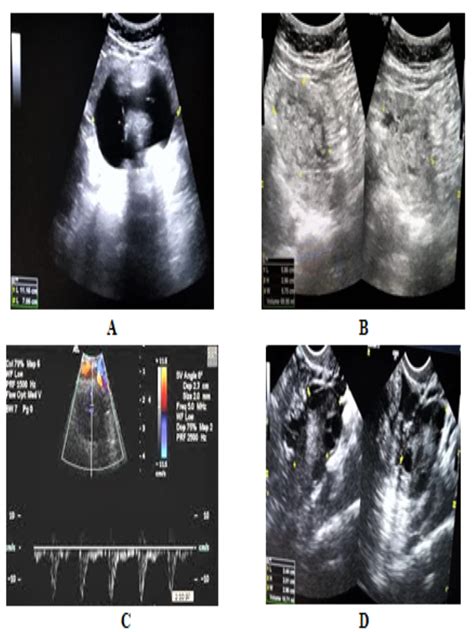

Diagnostic Approaches

Medical professionals use multiple techniques to identify and diagnose these unique tumors:

• Imaging tests (X-rays, MRI, CT scans) • Blood tests to check hormone levels • Biopsy to determine malignancy